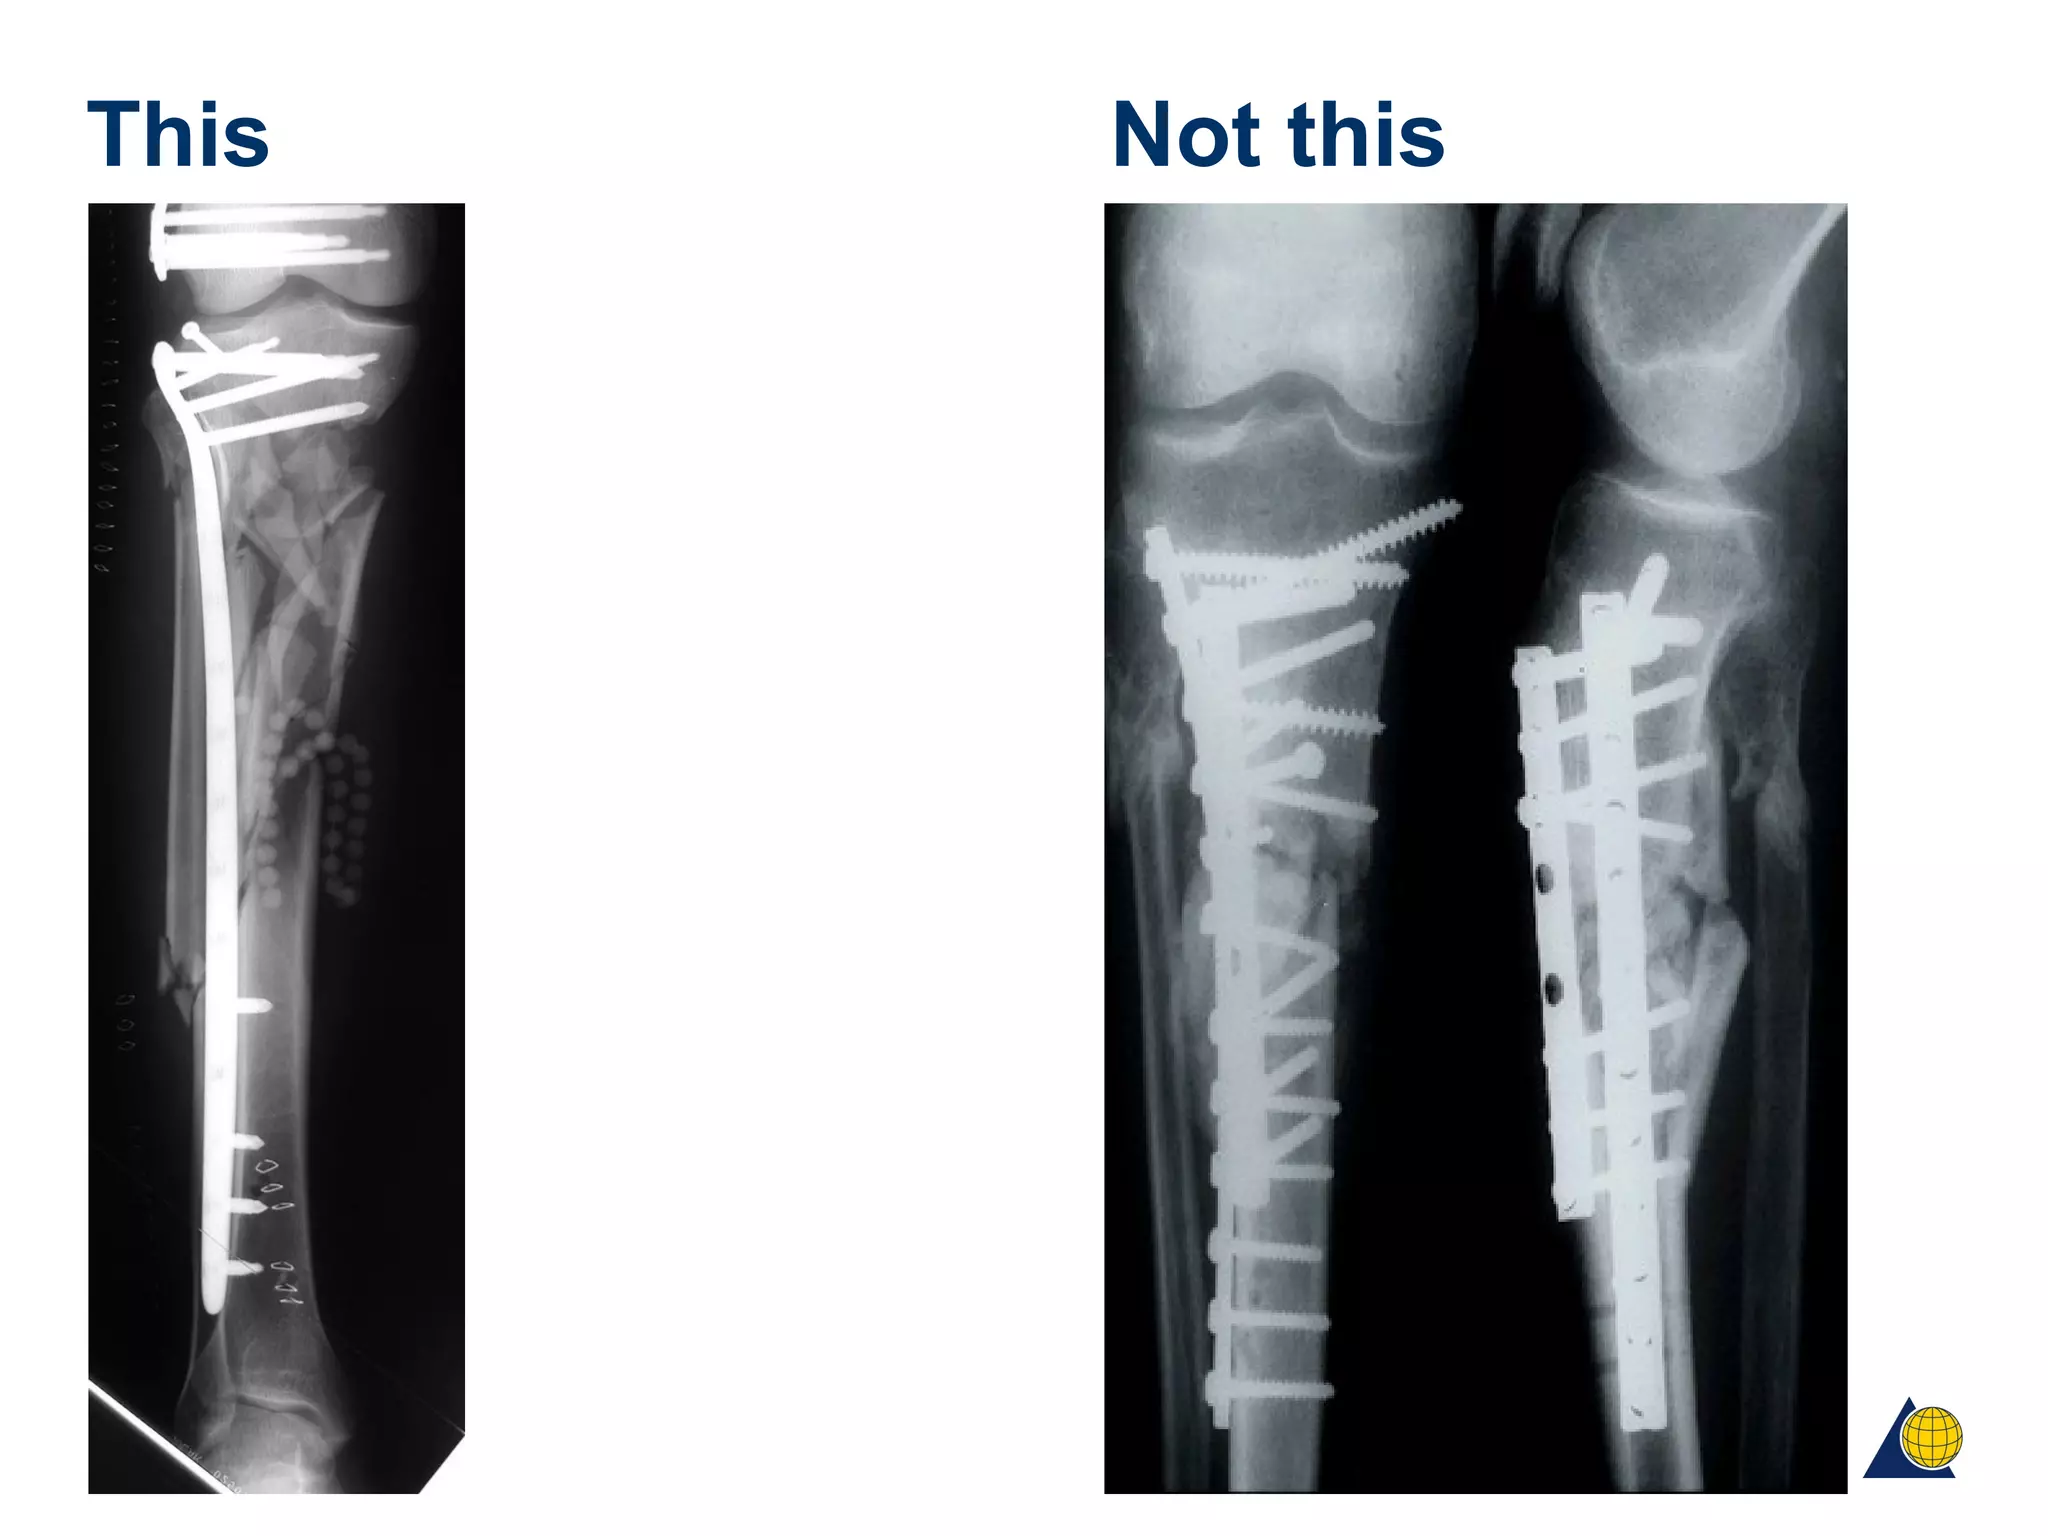

This Not this